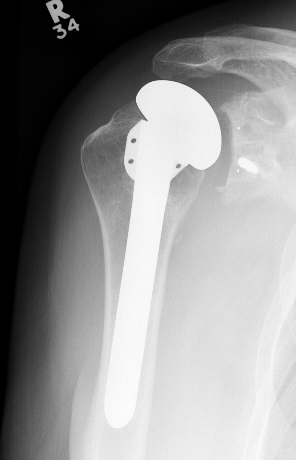

Aseptic loosening

TSR Loose glenoidaTSA loose glenoid

Glenoid Component LooseningHumeral resurface loose

Incidence

Schoch et al. JSES 2019

- 492 aTSA at 5 year follow up

- 308 (63%) had no radiolucent lines

- 184 (37%) had peri-glenoid lucency

- those with glenoid lucency had decreased ROM and patient-reported outcomes